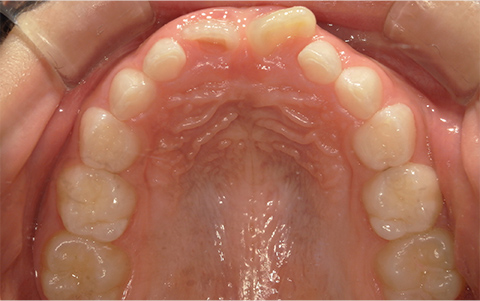

症例